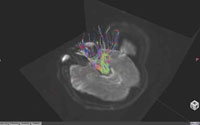

MRトラクトグラフィ(W.I.P.)

頭部における神経線維の軸策を追跡して描出する。線維が通過する領域を任意に指定することができ,テンソル方向ごとに色分けして表示をすることが可能である。MPR断面を合成できるので,病変部分などとの位置関係が把握ができる。